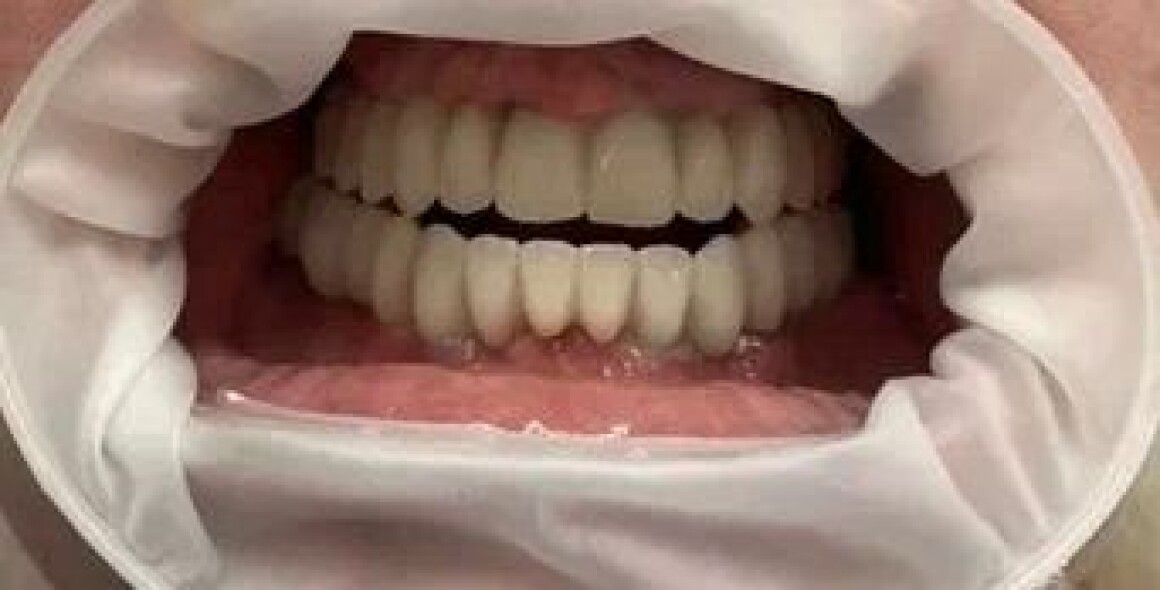

Имплантация и лечение от Александра Сергеевича

Тотальная реабилитация

Проблема : Полное отсутствие зубов, не держаться протезы

• Установка постоянной конструкции из металлокерамики верх и низ